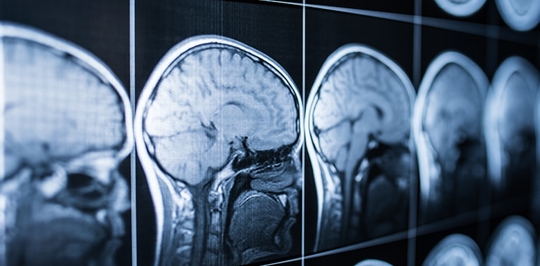

Head and brain injuries are common in car accidents because of the force against the body that is exerted in a wreck. When the head moves forward and back repeatedly or hits something hard, the brain can be slammed against the inside of the skull.

Traumatic brain injuries (TBIs) may be mild, moderate, or severe.